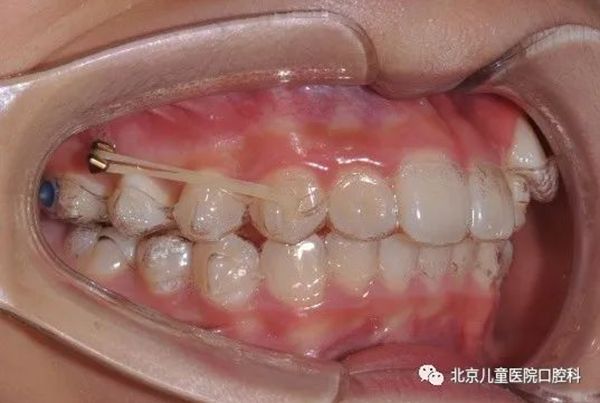

很多朋友都听说过牙齿矫正过程中要“打骨钉”,会联想到疼痛、流血等不适感,纷纷对我表示“很害怕”。众所周知,正畸过程中会用到多种器械与材料,比如托槽、钢丝、透明牙套、橡皮圈等等,还有越来越普及的我,学名“微种植体支抗”。今天就简单自我介绍一下。

骨钉是正畸过程中固定于骨组织上的小直径、头部独特设计的微螺钉,又叫支抗钉、种植钉。通常暂时性植入牙槽骨,矫正结束时取出。

骨钉的直径从1.2mm~2.7mm不等,矫正牙齿常用1.3mm~1.6mm直径的骨钉,长度多为4mm~12mm,目前正畸常用6mm~10mm长度的规格。由此可见我的身材很迷你。

骨钉顶部的形状设计各种各样,如托槽式、牵引钩式、纽扣式等等,满足正畸临床多样化的需求。

打骨钉有什么作用呢?简单说,骨钉是正畸移动牙齿过程中引入的外援,锚定于牙槽骨中,适用于直接移动牙齿,或承担移动牙齿产生的反作用力,在专业术语中称为“支抗”。在以往没有我的情况下,反作用力会直接或间接作用于不希望发生移动的牙齿上,对正畸疗效产生不良影响。我可以为大多数正畸患者提供足够的支抗, 获得医患均满意的疗效,且植入和取出操作简单, 植入部位灵活,因此临床应用日益广泛。